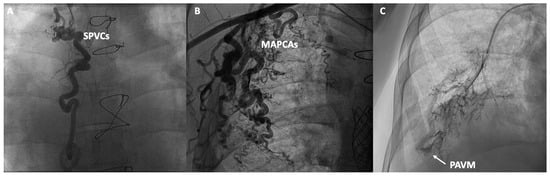

| Angiographies | Administration of iodinated contrast to anatomically evaluate the Fontan pathway and rule out potential obstructions, as well as SPVCs, fenestrations, and MAPCAs. |

| Bubbles contrast | Selective administration of agitated saline into the pulmonary branches, combined with echocardiography, to detect bubble passage into the cardiac chambers in the presence of PAVMs. |

| Collaterals | MAPCAs and SPVCs can be treated by embolization (using coils, microspheres, or liquid embolic systems), or occluded with vascular plug devices. |

| Intrapulmonary Shunt | Different techniques for redirecting hepatic flow to the pulmonary circulation could be useful in selected patients with severe intrapulmonary shunt in the context of diffuse PAVMs. |